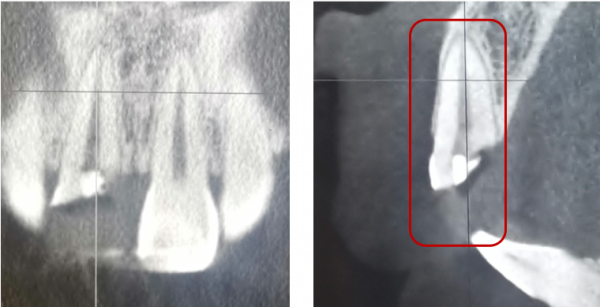

冠根折:累及牙釉質--牙本質--牙骨質折斷,累及牙釉質--牙本質--牙骨質--牙髓折斷

治療方案:方案(1)正畸或外科牽引4mm+冠延長+根管治療+樁核冠修復或根面覆蓋;方案(2)拔除患牙後種植修復;方案(3)意向性再植;方案(4)自體牙移植。